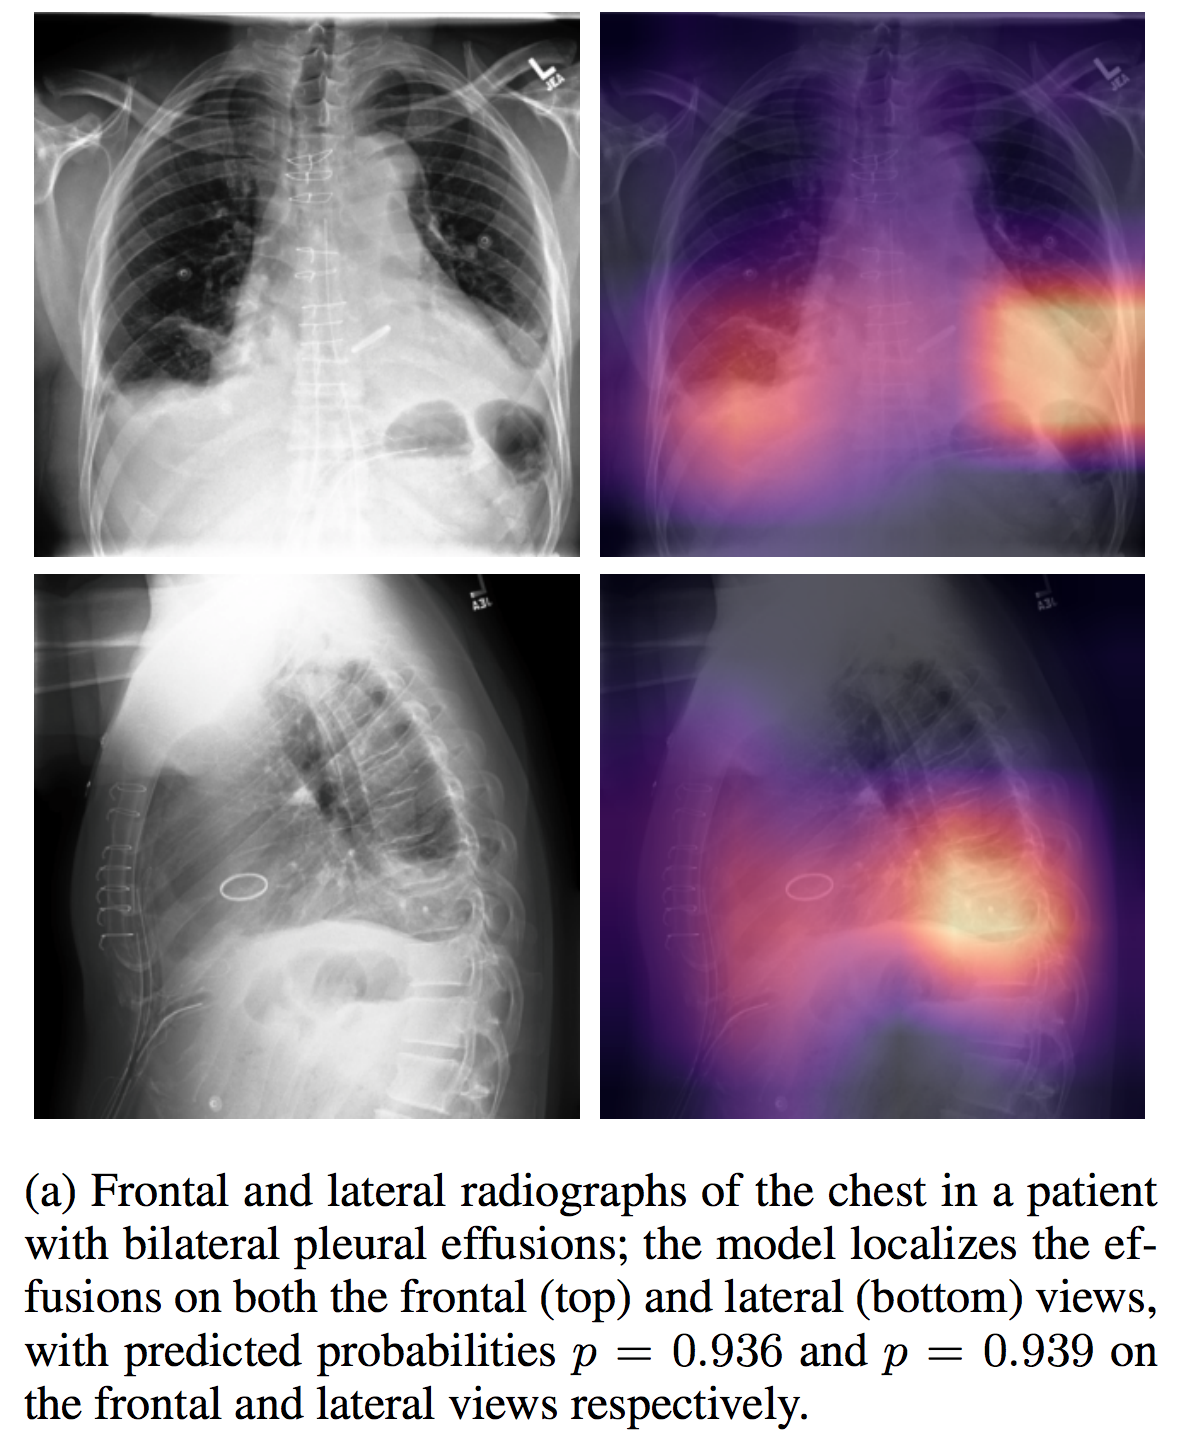

CheXpert

| CheXpert |

介绍论文: CheXpert: A Large Chest Radiograph Dataset with Uncertainty Labels and Expert Comparison

NIHChest Xray

| NIHChest Xray | CC0: Public Domain |